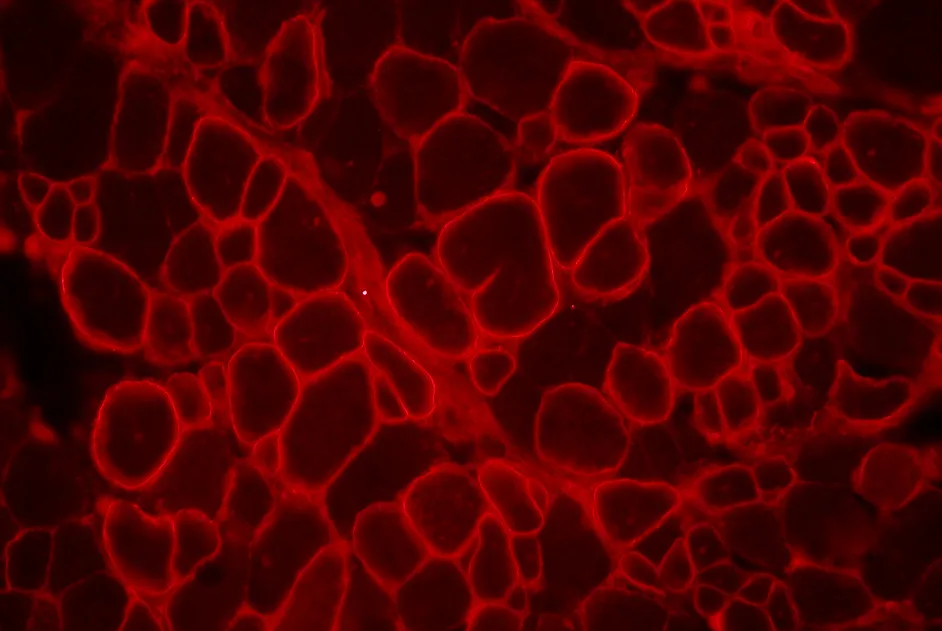

Les résultats ont mis en évidence l’efficacité du trans-épissage avec une restauration de la dystrophine et apporte ainsi la preuve de concept de l’efficacité de cette approche pour restaurer la dystrophine.

Cette approche a aussi permis d'obtenir de la dystrophine dans 2 modèles de souris de la DMD, la souris mdx (mutation dans l’exon 23 du gène de la dystrophine) et la souris mdx4Cv (mutation dans l’exon 53 du gène de la dystrophine) ainsi que dans des cellules musculaires de patients atteints de myopathie de Duchenne (DMD).